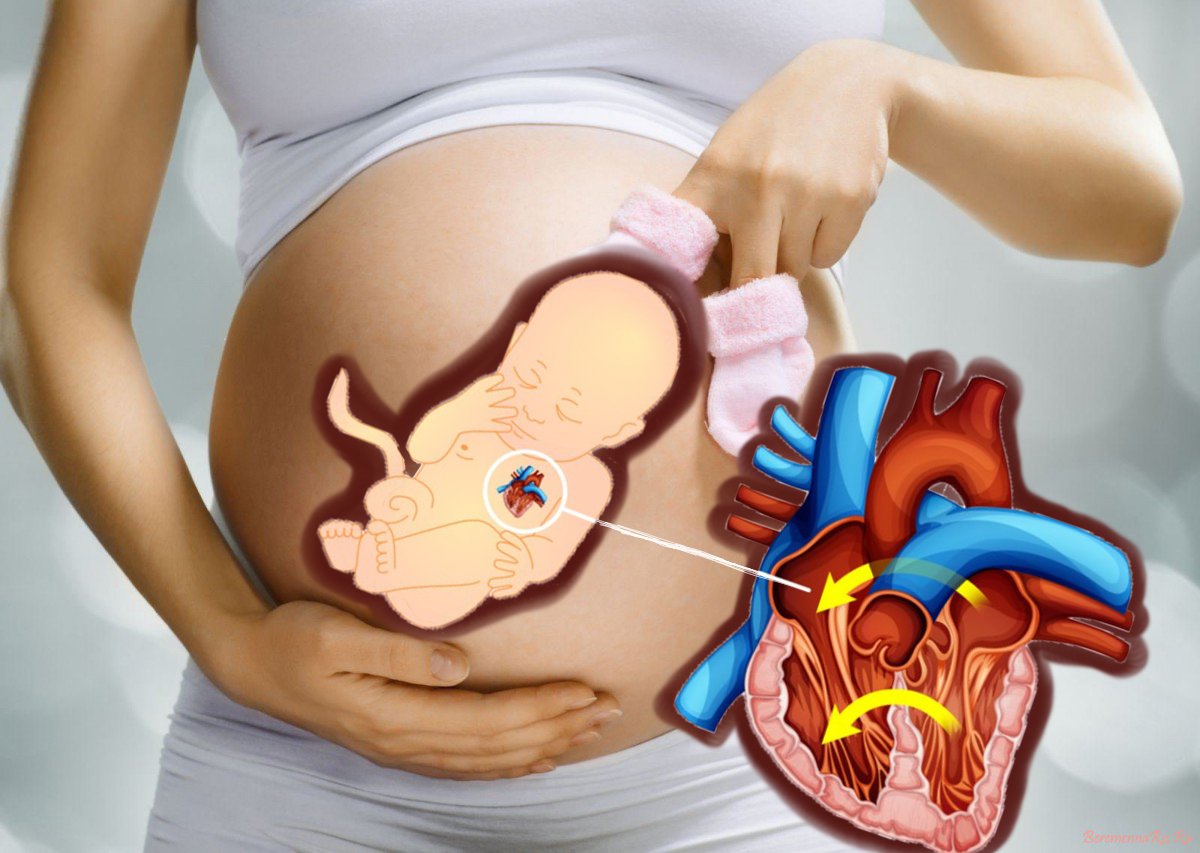

Пороки сердечно-сосудистой системы: виды и признаки